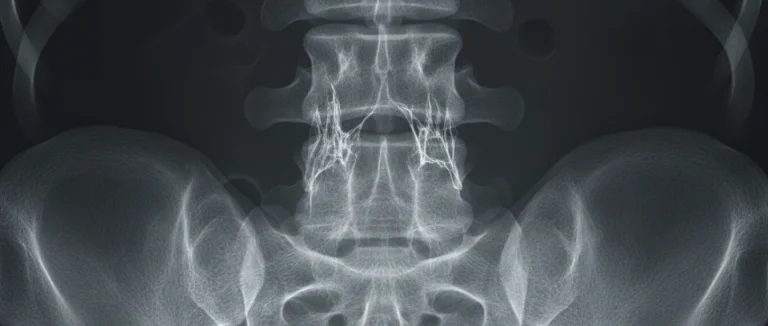

Самый надёжный способ определить уровни остеопороза – это измерение плотности костей с помощью двойной энергетической рентгеновской абсорбциометрии (DXA). Этот метод измеряет показатель BMD (bone mineral density) и сравнивает его с нормативными данными, получая T‑score и Z‑score.

Помимо общего BMD, врачи учитывают локальные результаты, например, в области поясничного отдела позвоночника и бедренных шейок, где риск перелома наиболее высок. Для более детального анализа иногда используют КТ‑сканирование или магнитно-резонансную томографию (MRI), но DXA остаётся золотым стандартом.